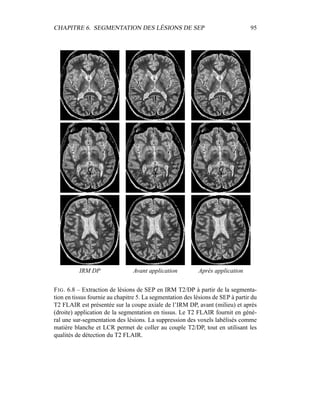

contre, les labélisations γk

i ne sont pas des labélisations floues ; les proportions

des γk

i des différentes classes pures n’ont a priori rien à voir avec la proportion en

termes de volume de chacun des tissus purs dans le voxel en question. Ceci nous